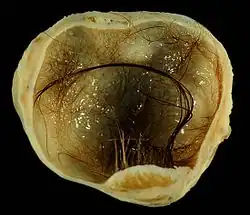

Immature (solid) teratoma

.jpg)

Immature, or solid, teratomas are the most common type of ovarian germ cell tumor, making up 40–50% of cases. Teratomas are characterized by the presence of disorganized tissues arising from all three embryonic germ layers: ectoderm, mesoderm, and endoderm; immature teratomas also have undifferentiated stem cells that make them more malignant than mature teratomas (dermoid cysts). The different tissues are visible on gross pathology and often include bone, cartilage, hair, mucus, or sebum, but these tissues are not visible from the outside, which appears to be a solid mass with lobes and cysts. Histologically, they have large amounts of neuroectoderm organized into sheets and tubules along with glia; the amount of neural tissue determines the histologic grade. Immature teratomas usually only affect one ovary (10% co-occur with dermoid cysts) and usually metastasize throughout the peritoneum. They can also cause mature teratoma implants to grow throughout the abdomen in a disease called growing teratoma syndrome; these are usually benign but will continue to grow during chemotherapy, and often necessitate further surgery. Unlike mature teratomas, immature teratomas form many adhesions, making them less likely to cause ovarian torsion. There is no specific marker for immature teratomas, but carcinoembryonic antigen (CEA), CA-125, CA19-9, or AFP can sometimes indicate an immature teratoma.[32]

Stage I teratomas make up the majority (75%) of cases and have the best prognosis, with 98% of patients surviving five years; if a Stage I tumor is also grade 1, it can be treated with unilateral surgery only. Stage II though IV tumors make up the remaining quarter of cases and have a worse prognosis, with 73–88% of patients surviving five years.[32]

Mature teratoma (dermoid cyst)

Mature teratomas, or dermoid cysts, are rare tumors consisting of mostly benign tissue that develop after menopause. The tumors consist of disorganized tissue with nodules of malignant tissue, which can be of various types. The most common malignancy is squamous cell carcinoma, but adenocarcinoma, basal-cell carcinoma, carcinoid tumor, neuroectodermal tumor, malignant melanoma, sarcoma, sebaceous tumor, and struma ovarii can also be part of the dermoid cyst. They are treated with surgery and adjuvant platinum chemotherapy or radiation.[32]